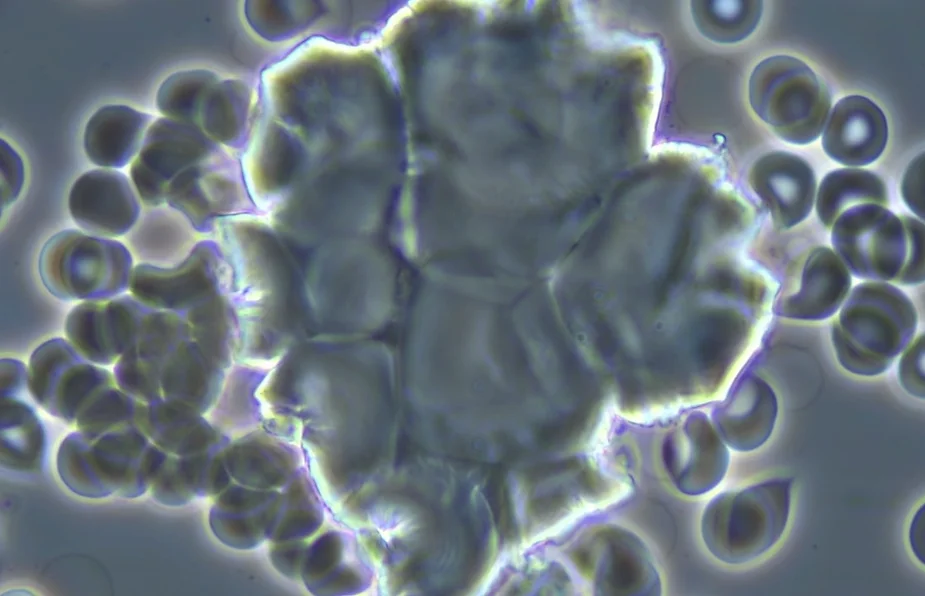

2. The micrograph below shows a symplast or a micro clot of enlarged red blood cells or a blood clot observed using a compound pHase contrast light microscope at 1500x magnification. These micro clots are now commonly seen in the live unstained blood of humans and animals due to acidic/toxic poison now found in food, water, air, vaccines, nutritional supplements and legend drugs. The hemoglobin, the molecule of the red blood cells adsorbs and absorbs metabolic, dietary, respiratory and environmental acidic poisonous waste in order to protect the delicate pH balance of the vascular fluids at 7.365 pH and -20.5 mV and the interstitial fluids that surround all body cells at a 8.4 pH and -80 mV. The red blood cells NOT the white blood cells are the primary protectors of the body cells that make up all organs, glands and tissues. White blood cell are secondary to red blood cells in providing immunity which is a major oversight in current medical microbiology.